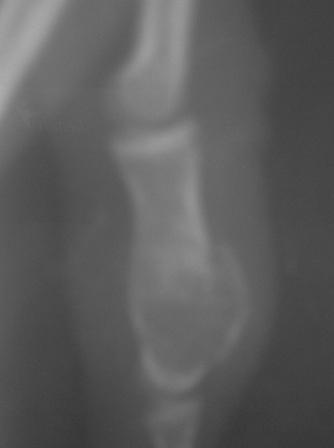

Уважаемые коллеги! Обратилась девочка 15 лет с жалобами на боли, отечности 4-го пальца кисти.

Заметила утолшение среднего фаланга 3 и 4-го пальцев 3,5-4 года назад, последний год начала чувствовать периодические боли, особенно в холодное дни, когда долго писала и всё. 4 дня назад получила легкий ожог пламенем кисти и пальцев, а 2 дня назад ударилась о волейбольный мяч и после этого в 4-м пальце нарастал отек , появилась резкая болезненность, усиливаюшийся при движении и пальпации, умеренная местная температура, а в 3-м пальце имеется утолшение среднего фаланга, следи ожога, безболезненный, отек м/тканей и местной температурй нет. Мы предполагаем ОБК, похоже и на фиброзную дисплазию, и краевой перелом сред. фаланга 4-го пальца и поэтому такая картина!

По рентгенограмме на ОБК не похоже.

Это энхондрома.

Стояние довольно приличное. Хорошо, что сохранили суставы. В такой ситуации вообще-то ничего и не придумаешь, кроме спиц. Поэтому я бы не менял метода фиксации. По снимкам больше похоже было на энхондрому, но вот меня смущает белесоватый цвет содержимого и кашицеобразная консистенция. Подождем гистологии.

А это и есть болезнь Олье! Как есть - классика. Она же - "энхондрома". Требует тщательного выскабливания и адекватного замещения. Хронос, аутокость - очень подходит. Не переживайте из-за тонких стенок, отбросьте эмоции по поводу "папиросной бумаги". Всё будет хорошо. Главное - спицы не забыть удалить вовремя. Болячка эта любит детей из близко родственных браков в изолированно живущих популяциях людей.